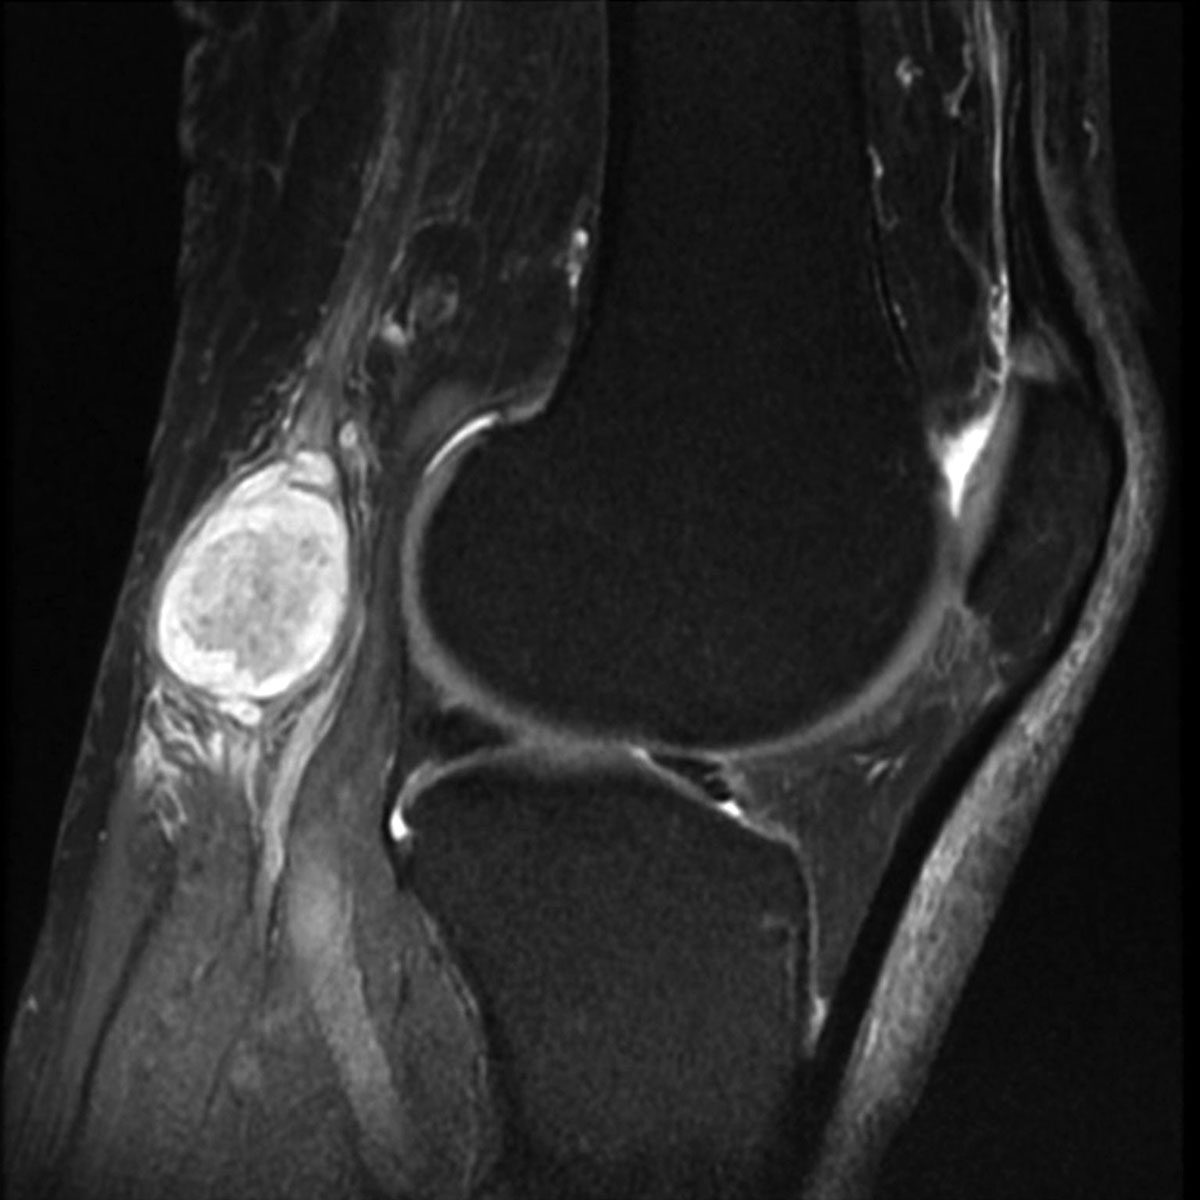

При появлении новообразования в области подколенной ямки необходимо обратиться к специалисту. Для точной диагностики могут потребоваться следующие методы:

- Компьютерная или магнитно-резонансная томография. Эти методы наиболее информативны, так как позволяют получить послойные изображения тканей сустава и определить состав жидкости в кисте.